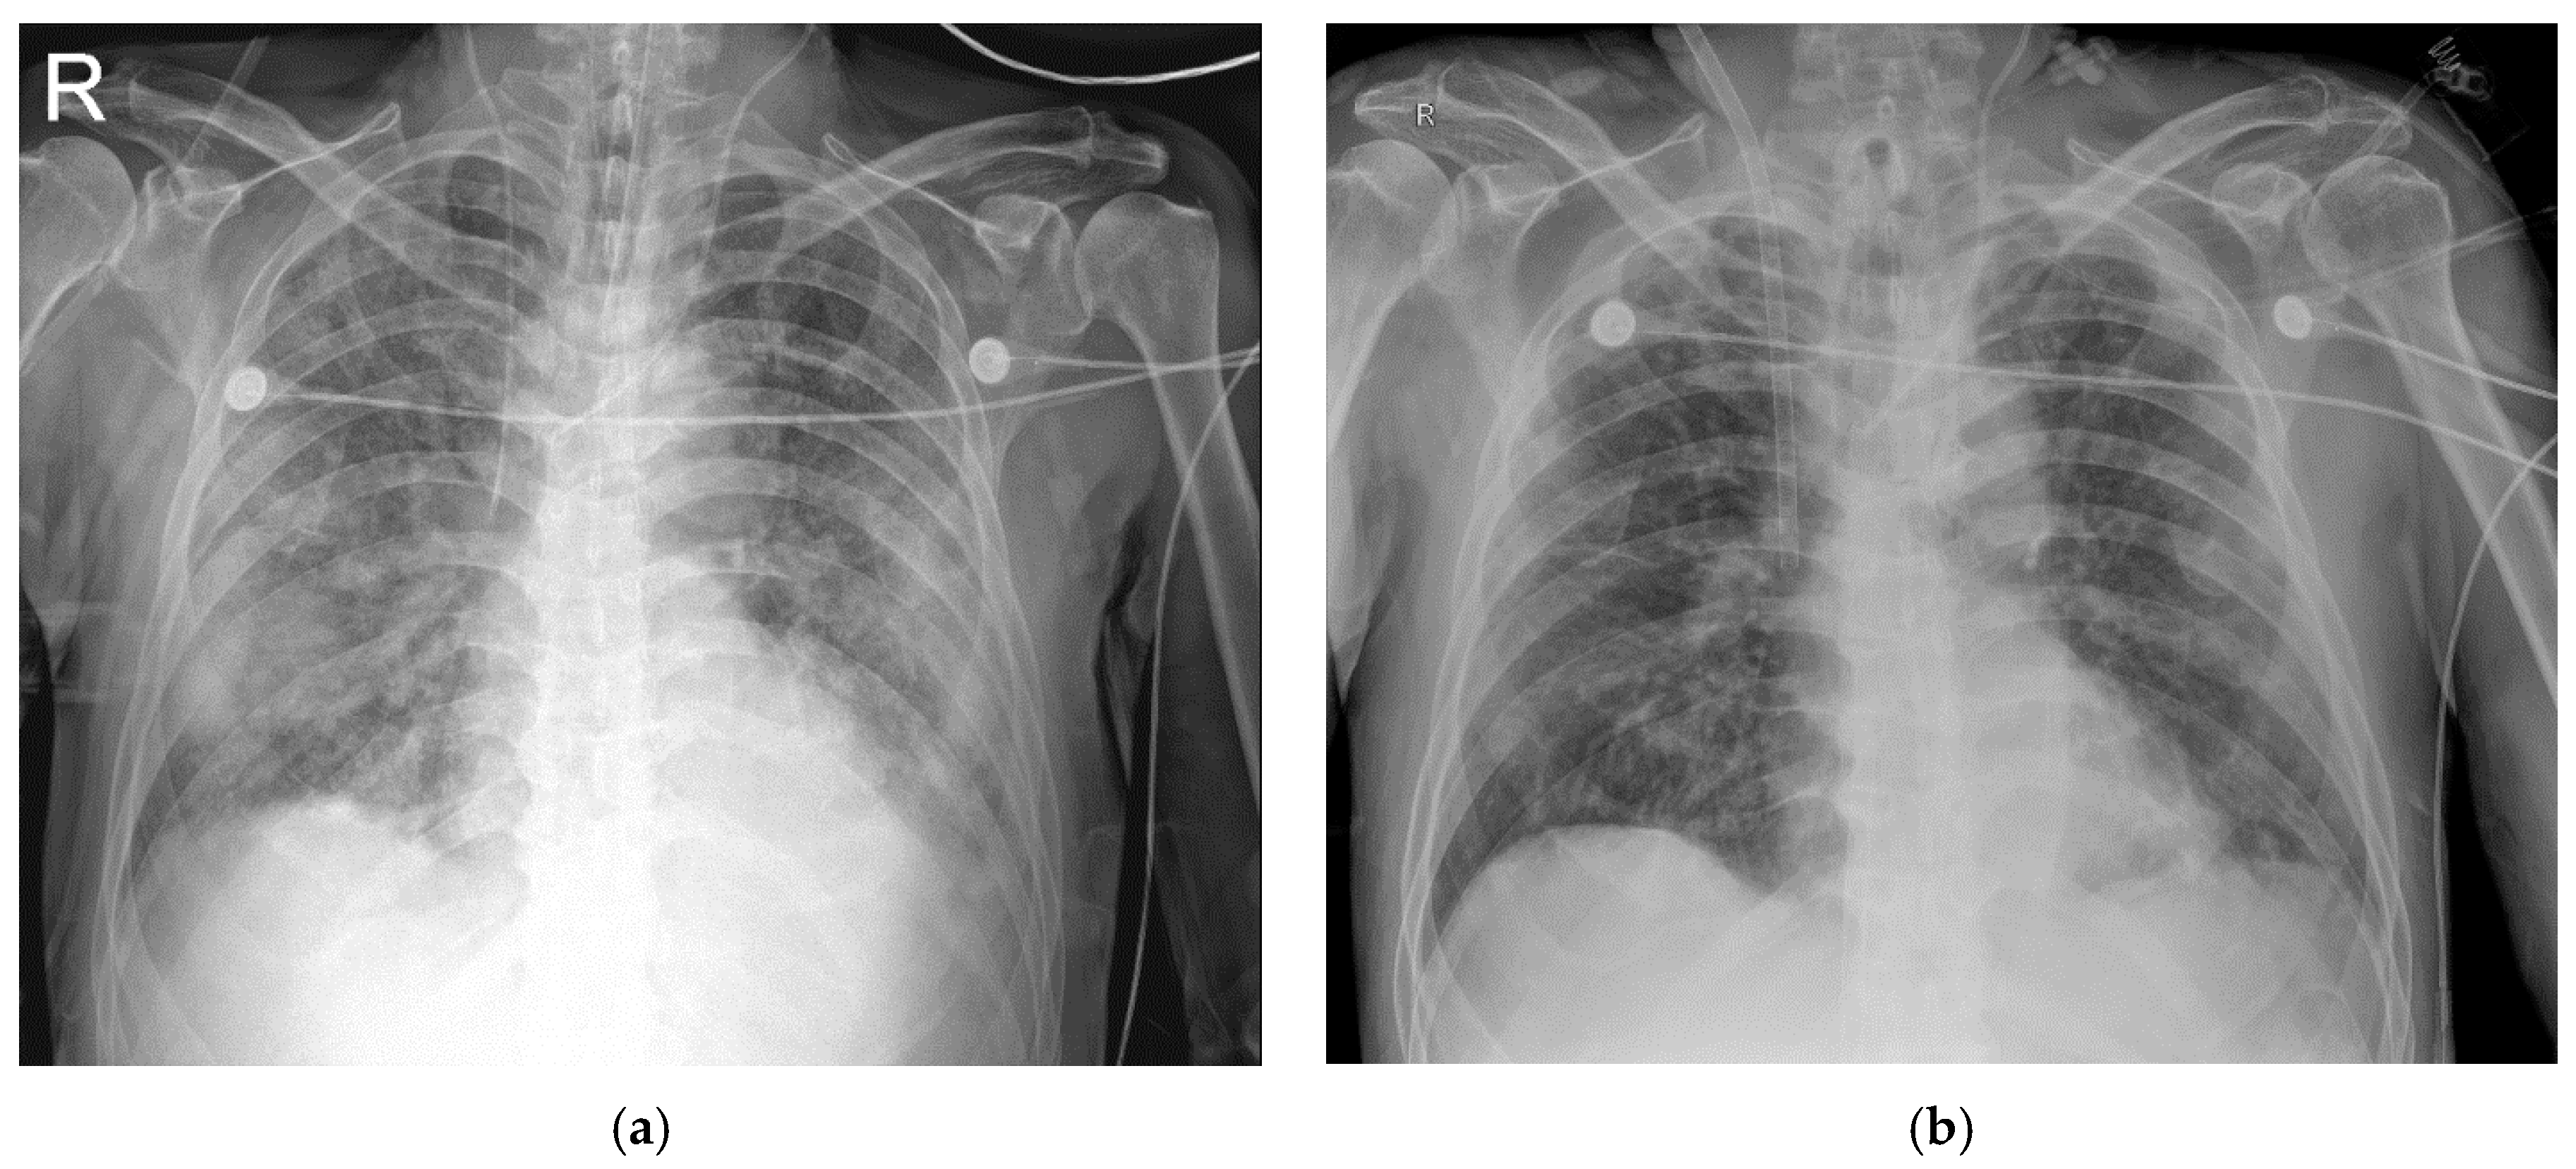

2.1. Case 1

2.2. Case 2

2.3. Case 3